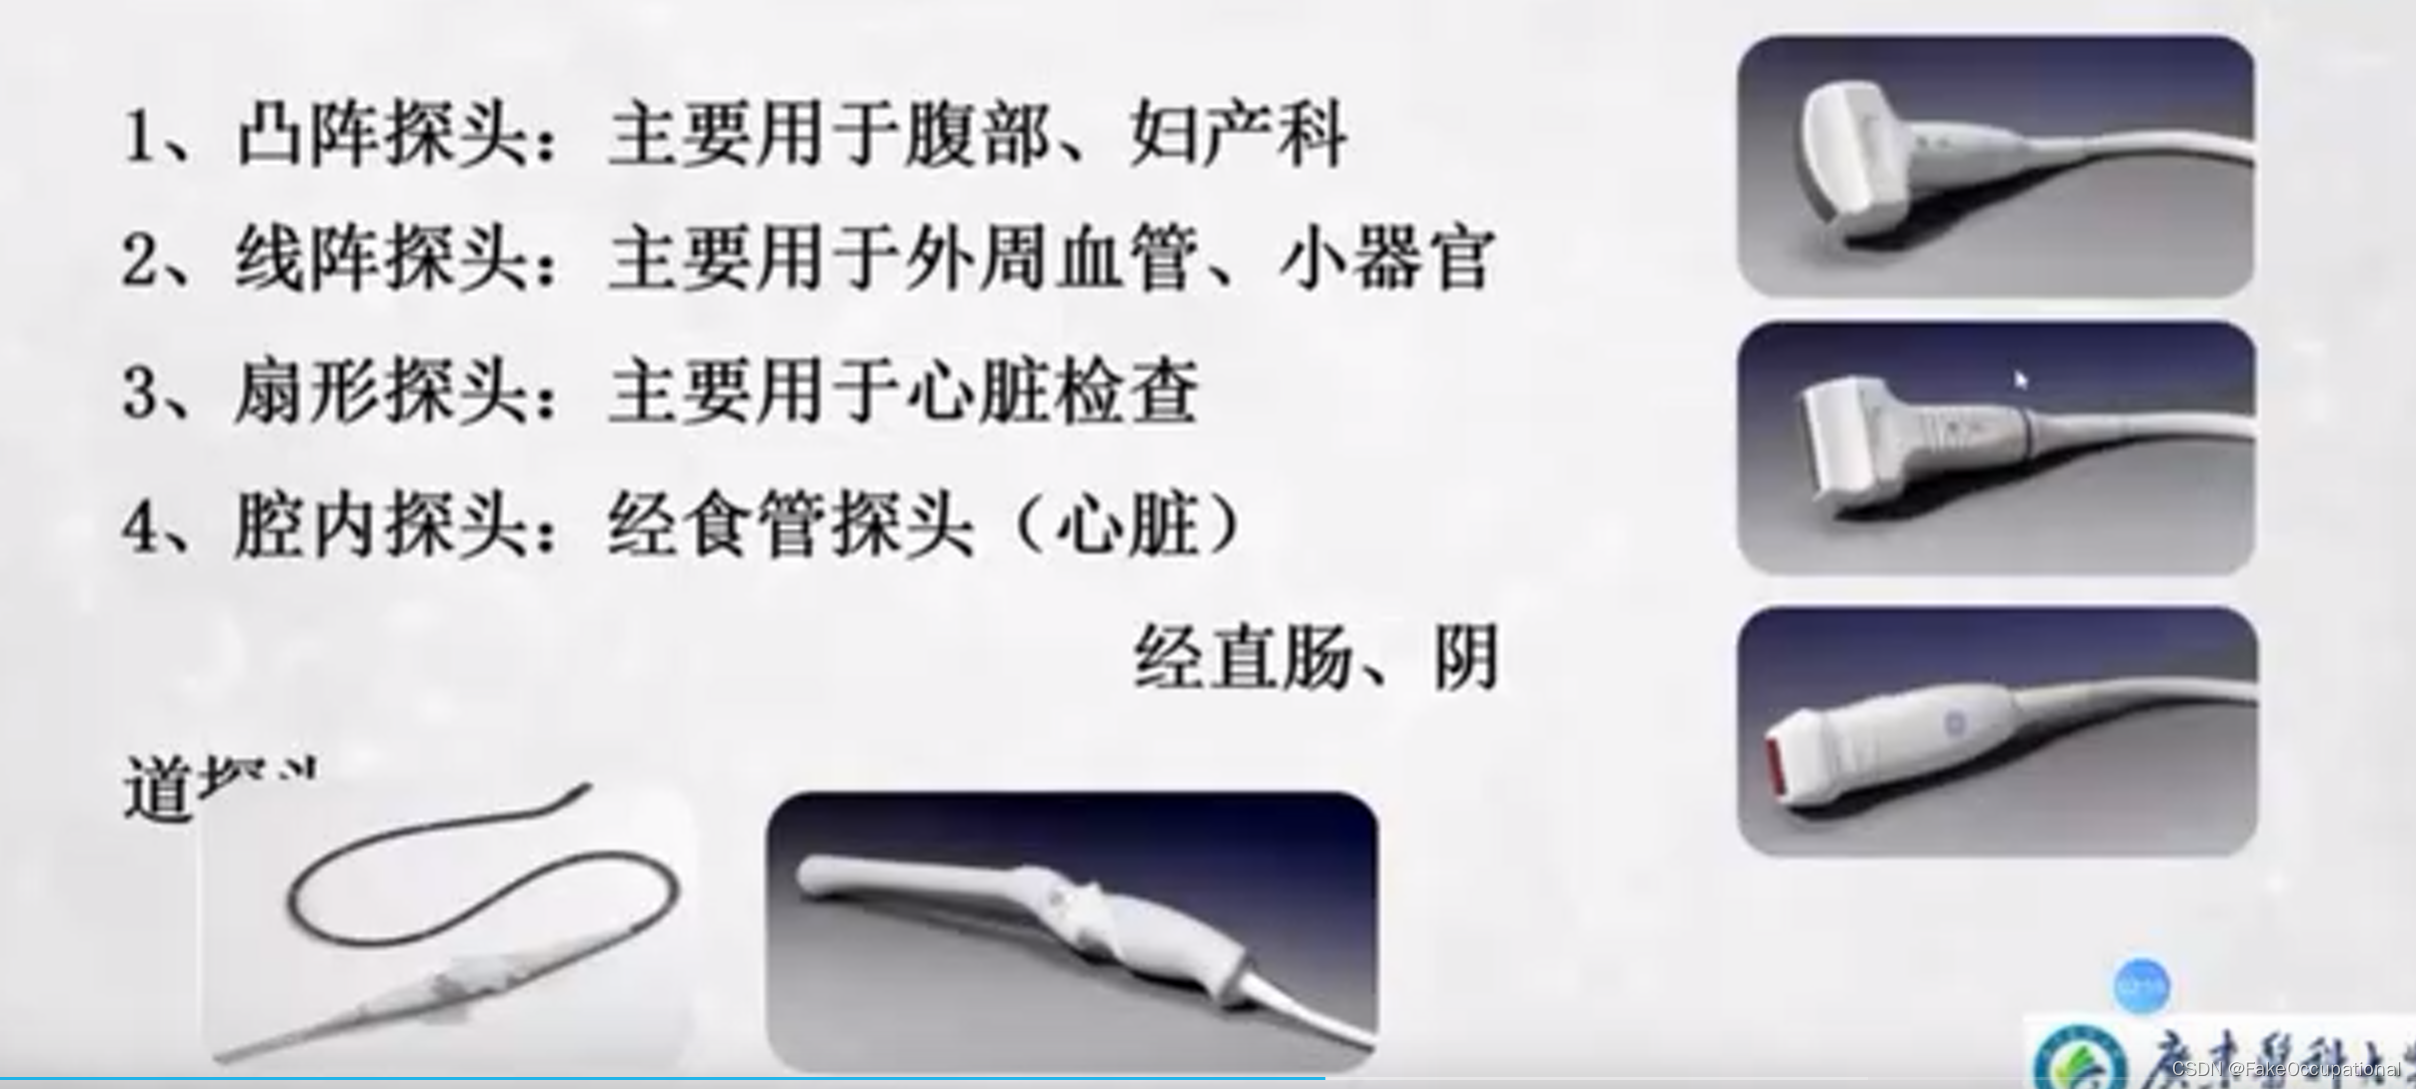

探头: 导线,匹配层,吸声背块,晶片

- 注:探头使用来自肝脏和心脏部分

探头使用

1、经腹壁探测

凸阵或扇形超声探头,成人选用频率3.5MHZ儿童选用频率5.0MHz

2、经会阴探测

小凸阵或扇形超声探头,成人选用频率3.5MHz儿童选用频率5.0MHz。

3、经直肠探测

选用双平面直肠探头或端射式直肠探头探头频率50MHz~10.0MHZ。